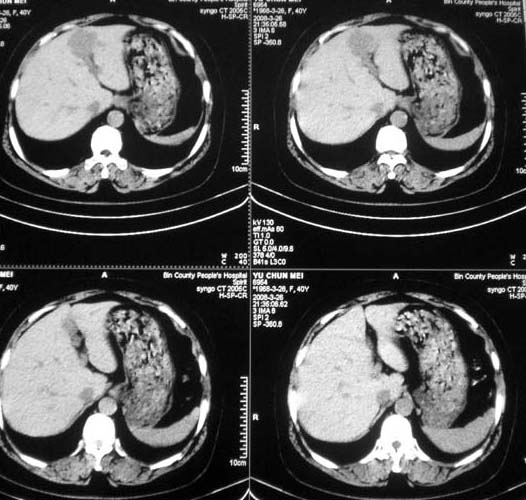

女,56岁,和上两个是同一病人,腹痛,胀痛,消化不良,五年前有血管瘤。密度减低影ct值为40hu。

肝内占位性病变:肝血管瘤可能性大,建议必须增强扫描。

肝内多发低密度影,边缘清楚,结合病史考虑:肝血管瘤可能性大,建议必须时增强扫描。